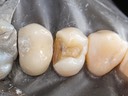

Chris Woo #3 prep